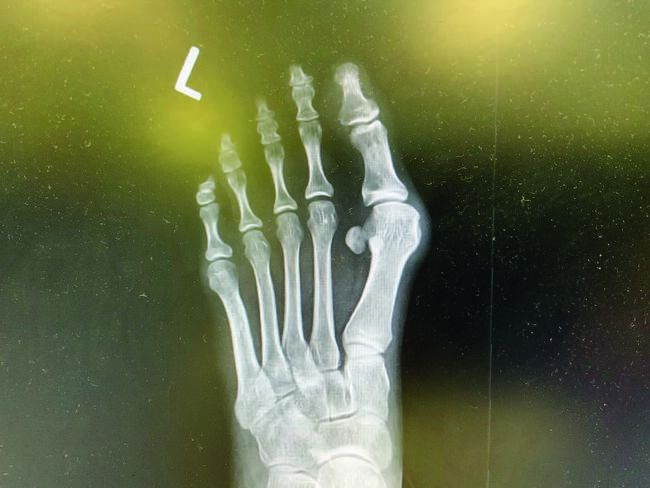

Standard radiographs allow further assessment of the bunion deformity, including anterior-posterior, medial oblique, and lateral weight-bearing. Further imaging may be necessary, and a sesamoid axial view looks at sesamoid position and frontal plane rotation of the metatarsal head as needed. Finally, in certain complicated or difficult cases that may have additional imaging needs, weight-bearing CT (computerized tomography) may help visualize the deformity in a three-dimensional fashion.